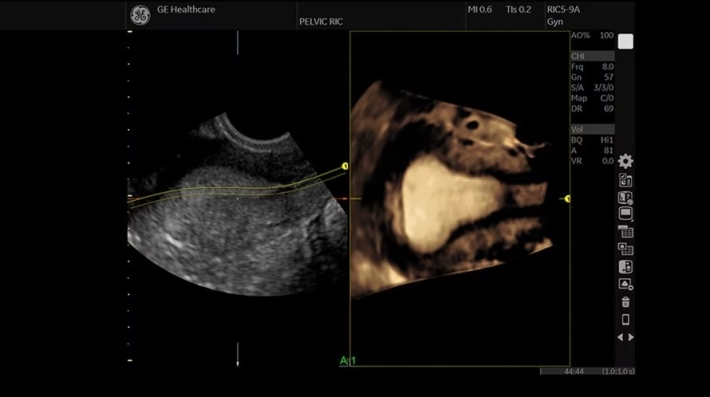

• RIC5-9A-RS — объёмный внутриполостной микроконвексный датчик;

• Advanced 3D — расширенная программа построения трехмерных изображений;

• Real Time 4D Kit — режим 4D-сканирования в реальном времени;

• Tomographic Ultrasound Imaging (TUI) — программа получения томографических срезов объемного УЗИ-изображения;

• VOCAL (Vol Calc) — программа автоматических расчётов объема с использованием 3D/4D;

• VCI Static — режим объёмного контрастного изображения;

• STIC — режим пространственно-временной корреляции изображения;

• Omniview — режим улучшенной визуализации в любой проекции;

• HDLive — режим HDlive в 3D и 4D с виртуальным источником освещения.